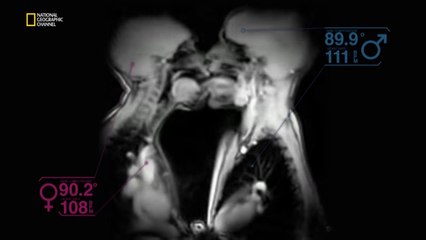

Kal Penn ile Büyük Resim - Dürtüler